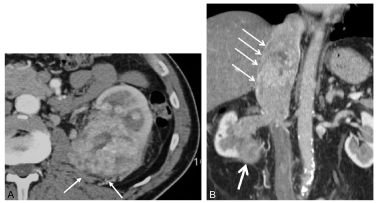

Fig. 31.5 Exemples de carcinome rénal évolué localement.

Scanner après injection de produit de contraste iodé au temps artériel (A, flèches) d’un volumineux carcinome rénal à cellules claires du rein gauche infiltrant la graisse périrénale. Scanner en reconstruction coronale après injection de produit de contraste iodé au temps tubulaire d’un carcinome rénal droit (B, flèche épaisse) avec envahissement veineux de la veine cave inférieure (flèches fines) jusqu’à l’atrium droit.

Source : CERF, CNEBMN, 2022.